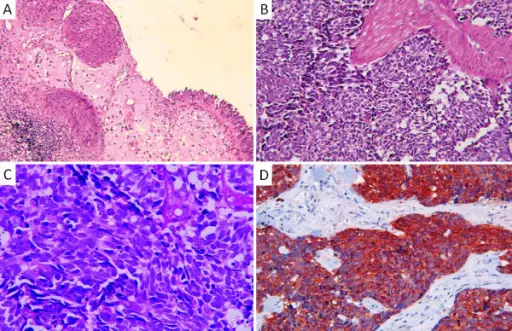

Squamous Cell Carcinoma of the Bladder

The second most prevalent type of bladder cancer is squamous cell carcinoma (SCC) of the bladder.

Squamous cell carcinoma (SCC) of the bladder is characterized by abnormal, accelerated squamous cell proliferation.

The normal bladder surface is not coated with squamous epithelium, hence this cancer develops against a backdrop of squamous metaplasia.

Symptoms of squamous cell carcinoma (SCC) of the bladder include:

- Chronic cystitis in older women

- Infection with Schistosoma haematobium in Egyptian males

- Persistent nephrolithiasis

Adenocarcinoma of the Bladder

Adenocarcinoma of the bladder is a type of bladder cancer due to malignant glandular cells.

Adenocarcinoma of the bladder may arise from:

- Cystitis glandularis

- Exstrophy

Cystitis glandularis is associated with a urachal remnant and causes adenocarcinoma of the bladder that develops near the dome of the bladder.

Exstrophy is a congenital failure to form the caudal portion of the anterior abdominal and bladder walls.